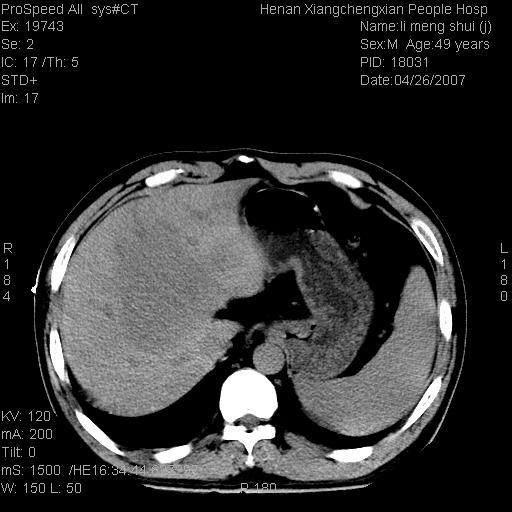

| 患者,男,49岁, 腹疼伴恶心\\呕吐20天,20天前无明显诱因出现右上腹部疼痛,钝疼,无放射,伴恶心\\呕吐,不伴发热.患者不愿增强. b超:肝脏右叶实性占位. ct:肝脏右叶可见一巨块状圆形低密度影,大小约93mm*84mm,其内可见点状高密度影,胆囊、胰腺、脾脏大小、形态及密度未见异常,腹膜后间隙未见肿大淋巴结影。 印象:肝脏右叶巨大肿块,性质待定,建议增强并穿刺活检进一步确诊。 ct平扫: ![]() ![]() ![]() ![]() ![]() ![]() ![]() ![]() ![]() ![]() ![]() ![]() ![]() ![]() ![]() ![]() ![]() 肝脏右叶肿块ct引导下穿刺活检术 患者于16时05分仰卧于ct检查台上,首先行肝脏ct扫描确定进针位置、深度、角度。在局麻下行ct引导下肝脏右叶肿块穿刺活检术。常规消毒、铺巾、局麻。在ct引导下使活检针经右侧腋中线、第9肋间隙垂直胸壁进针90mm,针头进入病变预定位置。在病变预定位置多点、多方向抽取小米样病变组织多块,涂片五张送病理检查。术后穿刺点局部无出血,未出现腹腔积液等并发症。术中及术后患者生命体征稳定,手术于17时10分成功完成。患者安返病房。 穿刺片 ![]() ![]() ![]() ![]() ![]() ![]() ![]() ![]() ![]() ![]() ![]() ![]() ![]() ![]() ![]() ![]() 病理结果肝细胞癌 ![]() 原贴地址:http://www.radinet.com.cn/forum_view.asp?forum_id=4&view_id=24130 ok |